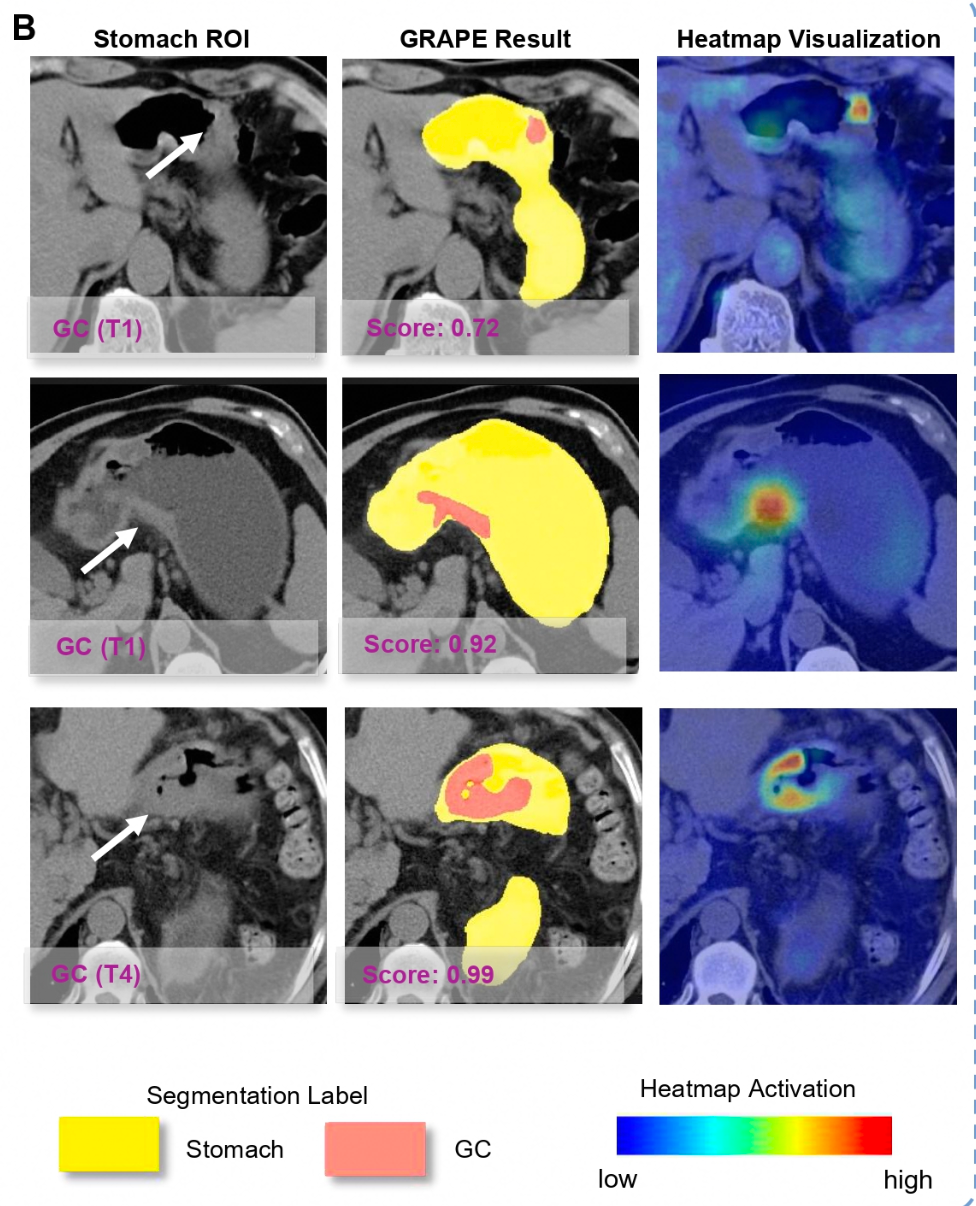

最终的解决方案是开发了能专门识别胃黏膜层细微变化的深度学习模型。这个模型不仅能发现明显的肿瘤,还能识别各个阶段的胃癌,从最早期的T1期到晚期的T4期都能搞定。

现在医生怎么用这个AI呢?实际工作中,AI会先对腹部平扫CT做初筛,标记出可疑区域,然后医生再对这些高风险人群做胃镜确诊。这样既能提高效率,又不会漏诊。